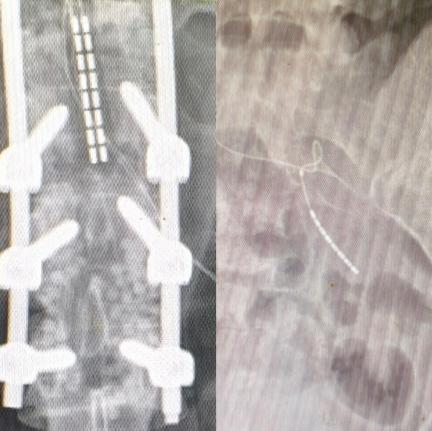

经过临床、影像与电生理等多维度精细评估,我们为她量身定制了SCS(脊髓电刺激)+ SNM(骶神经调控)双电极系统植入手术:一片外科电极覆盖胸腰段,旨在唤醒下肢的感觉与运动;另一根针状电极植入骶神经孔,专攻大小便功能重建。手术顺利,电极精准就位,术后虽然出现一过性发热,但很快恢复平稳。

双电极位置精准